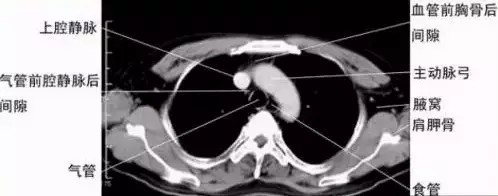

【核磁共振:功能强悍,无辐射】

成年人体体重水占比达到70%,这意味几乎每一个人体器官当中都有水这个元素。1个水分子由2个氢原子和1个氧原子组成——人体内含有大量的氢原子,每个氢原子都有自己的氢核。

上文所述的“小陀螺”,精确到人体内的就是氢核。心脏、肝脏、肾等等每一个器官内氢核的旋转速度、方向都不一样。把人体放置在均匀磁场内,这些氢核会吸收电磁波的能量,最终能量达到一致而发生共振——这就是人体内的核磁共振。

当均匀磁场撤离后,每一个器官释放出的能量各不相同,核磁共振的成像原理,正是通过感应器官释放出的能量不同而得出结果的。

健康的每一个相同器官,经过核磁共振后释放出的能量是相同的。每个器官都有一个核定健康的“能量值”。当患者完成核磁共振之后,医生正是通过比对患者的“能量值”与标准能量值的差异来判断病变与否。

“横看成岭侧成峰,远近高低各不同”,苏轼用来描写庐山的名句,其实很多时候也可以用来形容病变区域。对病变区域的观察,横看、侧看、上看、下看对结果都有着不同影响。医生要想全面、细致的了解病变区域的“全貌”,就要求检查手段能够提供不同方向的成像。

核磁共振的一个巨大技术突破,就是可以对人体进行横断面、矢状面、冠状面三维任意角度切层,这就保证了医生只要有需要,可以从任何角度观察病变区域。除此之外,没有电离辐射也是核磁共振的一大优势。

核磁共振检查的范围、准确率都比X光、CT强大,这也是为什么核磁共振很贵的原因。核磁共振在骨骼、肌肉和器官的检查上都有相当的价值,并且核磁共振的核心优势是对软组织的检查更准确——这也是足球运动员肌肉拉伤、韧带损伤等疾病都拍核磁共振的原因。此外,核磁共振对颅脑、脊柱和脊髓等的解剖和病变的显示,也比CT更好。